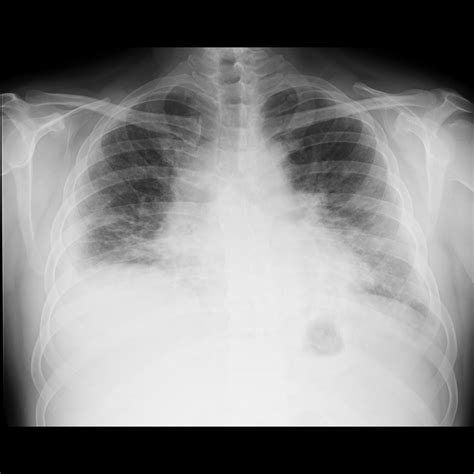

While the Pulmonary Edema Cxr is excellent at confirming the presence of fluid, determining the etiology is equally important. Cardiogenic pulmonary edema is typically associated with a widened cardiothoracic ratio (cardiomegaly) and vascular redistribution. In contrast, non-cardiogenic pulmonary edema, often seen in Acute Respiratory Distress Syndrome (ARDS), usually presents with a normal heart size, patchy or peripheral infiltrates, and an absence of pleural effusions.

Clinicians utilize the X-ray in conjunction with lab tests like Brain Natriuretic Peptide (BNP) to make a definitive diagnosis. If the heart shadow is enlarged, it strongly suggests a cardiac origin, whereas a normal-sized heart with widespread bilateral infiltrates warrants an investigation into sepsis, transfusion-related lung injury, or other non-cardiac triggers.

Once the Pulmonary Edema Cxr confirms the diagnosis, management usually involves the administration of loop diuretics, vasodilators, and oxygen therapy. The imaging serves as a baseline to monitor the patient's response to therapy. Following treatment, a repeat chest X-ray is often ordered to observe the "clearing" of the lung fields, which usually occurs as the patient achieves a negative fluid balance.

Persistent opacities despite adequate diuresis may suggest complications such as pneumonia, lung collapse, or a non-cardiogenic component to the pulmonary edema. Regular assessment through imaging ensures that the treatment plan is effectively targeting the underlying cause of the fluid overload.

In summary, the diagnostic power of the chest X-ray remains unmatched for its accessibility and speed in clinical environments. By identifying specific signs like cephalization, Kerley B lines, and alveolar opacities, healthcare providers can swiftly categorize the severity of pulmonary edema. While the Pulmonary Edema Cxr is a cornerstone of diagnosis, it must be interpreted alongside clinical symptoms and hemodynamic markers to ensure accurate patient care. Through systematic evaluation and an understanding of the radiographic progression of fluid accumulation, clinicians can effectively manage fluid overload and improve patient outcomes in high-stress, acute care settings.